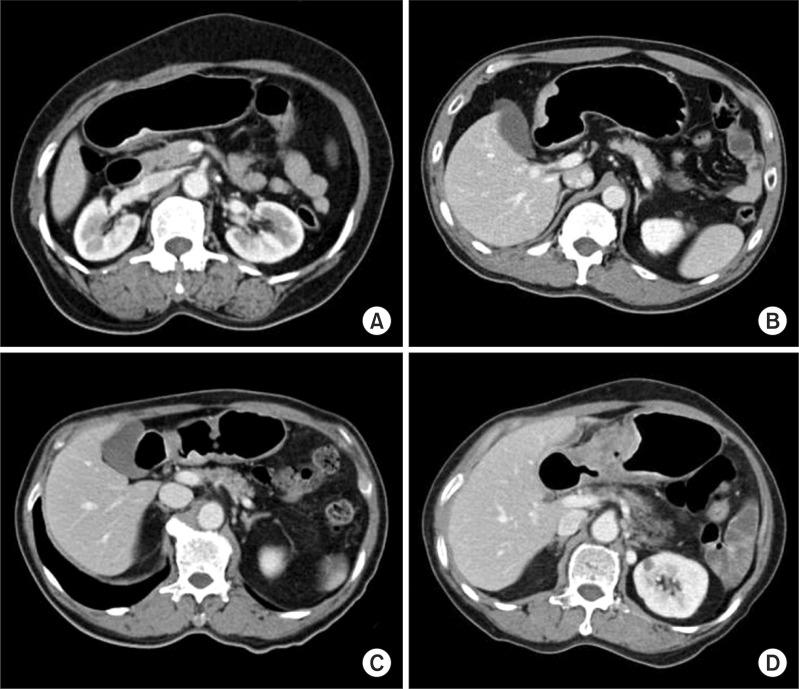

The predictive values for pT1 of endoscopy and computed tomography were 90.0% and 89.4%, respectively. In detail, the predictive values of endoscopy for pT1a, pT1b, and pT2 or more were 87%, 58.5%, and 90.6%, respectively. The predictive values of computed tomography for pT1a, pT1b, and pT2 or more were 68.8%, 73.9%, and 84.4%, respectively. The factors leading to underestimation of pT2 or more lesions by gastroscopy were the middle third location, the size greater than 2 cm, and younger age. Those for overestimation of pT1 lesion by computed tomography were male, age more than 70 years, elevated type, and size greater than 3 cm.

内镜和计算机断层扫描对 pT1 的预测值分别为 90.0%和 89.4%。具体而言,内镜对 pT1a、pT1b 和 pT2 或更高的预测值分别为 87%、58.5%和 90.6%。计算机断层扫描对 pT1a、pT1b 和 pT2 或更高的预测值分别为 68.8%、73.9%和 84.4%。导致内镜低估 pT2 或更高病变的因素是中三分之一位置、大于 2cm 的大小和较年轻的年龄。导致计算机断层扫描高估 pT1 病变的因素是男性、年龄大于 70 岁、隆起型和大于 3cm 的大小。